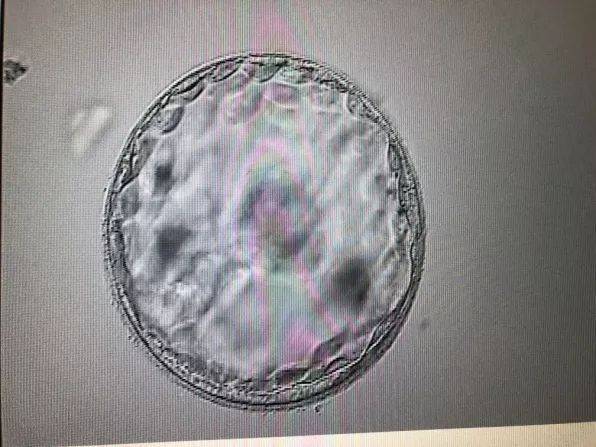

卵子质量差会增加流产的风险。这是因为卵子异常会导致胚胎发育不良,无法正常着床或维持妊娠。